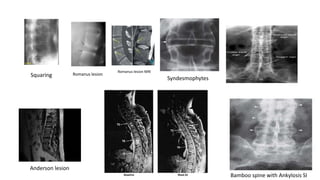

• Lateral thoracolumbar spine X-rays : Findings may be

1. Suarring of verterae

2.Shiny corners(Romanus lesion)

3.Spondylodiscitis(Anderson lesion)

4. Syndesmophytes with partial or complete fusion

5.In advanced disease, ossification of the anterior longitudinal ligament and facet joint

fusion may also be visible

6.Bamboo spine appearance(Combination of mentioned feature)

Syndesmophytes

Bamboo spine with Ankylosis SI

Squaring Romanus lesion

Anderson lesion

Romanus lesion MRI